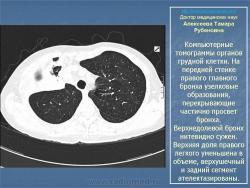

Доктор медицинских наук  Алексеева Тамара Рубеновна

Туберкулез внутригрудных лимфатических узлов.